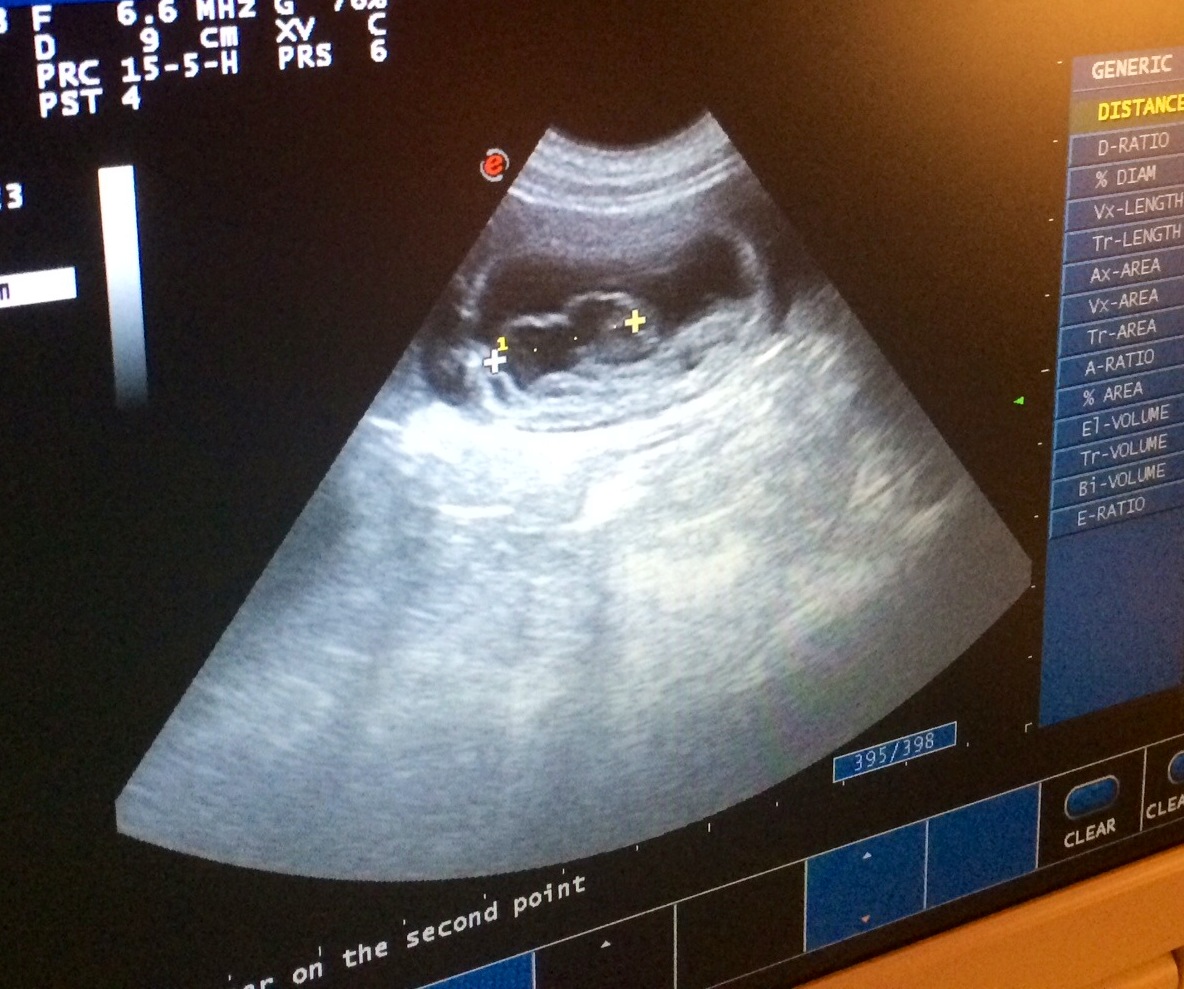

Vi har vært på ultralyd…

og gleden er stor, for det viser seg at Bitten er drektig! Undersøkelsen viste at hun venter et middels stort kull, antakelig 4-6 valper 🙂

Fostrene er nå omtrent 1,7 cm lange, og man kan se fosterposer og små hjerteslag 🙂 Her kommer noen bilder fra ultralydundersøkelsen. Fotograf er Tommy Bratteng.